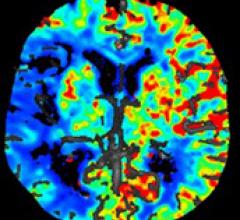

Computed tomography (CT) systems use a series of X-ray images to create an image volume dataset with slices that can be manipulated on any plane using advanced visualization software. The section includes computed tomography scanners, CT contrast agents, CT angiography (CTA and CCTA), CT perfusion, spectral CT (dual-source CT), and iterative reconstruction dose reduction software.

Advancements in newer 64-slice computed tomography (CT) systems and the introduction of 256- and 320-slice systems are ...